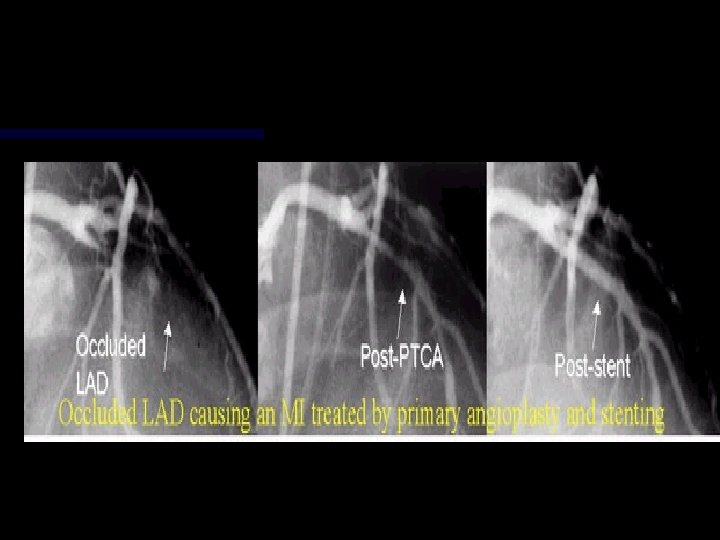

Thrombolytics TPA n Retavase n Streptokinase n n Door -to-Drug Time n Time is Muscle!